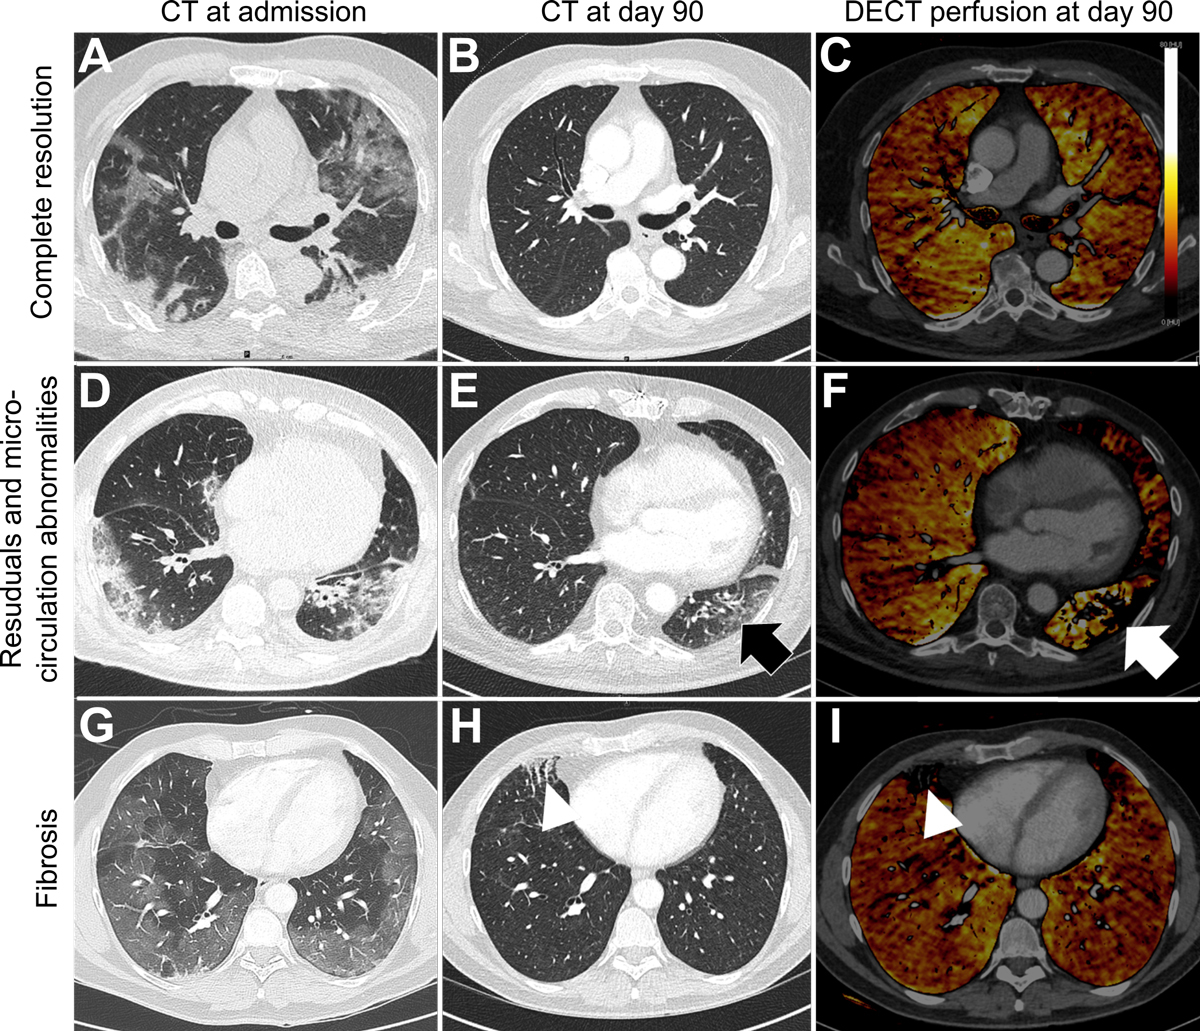

CT scans showed residual abnormalities in 21 of 35 patients (60%), 7 of whom also had signs of fibrosis (fig. 3), with similar distributions between ICU and non-ICU patients and no correlation to pulmonary function tests. No pulmonary embolism or further thromboembolic events occurred after acute hospital care.

Figure 3 Evolution patterns of chest CT findings from admission to day 90.

Axial CT images (A, B, D, E, G, H) and DECT overlay maps (C, F, I) presenting three evolution patterns of lung involvement from admission to day 90 observed in COVID-19 patients after treatment with tocilizumab.

(A) Axial CT image is depicting a 62-old male patient with bilateral GGO and consolidations 3 days after onset of symptoms with complete resolution at day 90 (B) and no microcirculation abnormalities (C).

(D) Axial CT image of a 78-old male patient 4 days after symptom onset showing bilateral GGO and reticulations (E) which seem to be associated with microcirculation abnormalities on DECT (F) at day 90. 49-old male patient receiving ECMO presenting profound bilateral mosaic pattern with GGO (G) 3 days after onset of symptoms showing focal fibrosis characterized by course reticulations and traction bronchiectasis (H) which correlates with focal perfusion defects on DECT (I) at day 90.

GGO = ground glass opacity; DECT = dual energy computed tomography